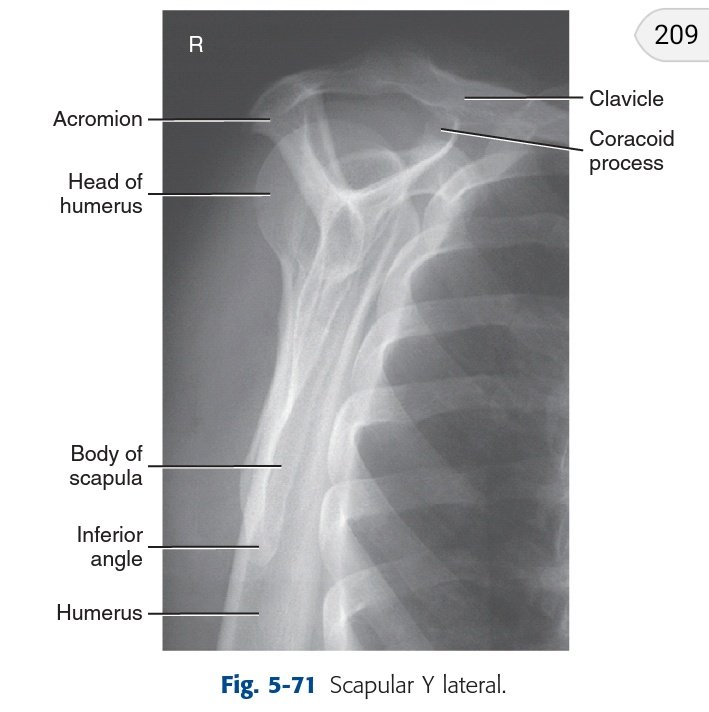

☆فحص الكتف

☆Shoulder x ray

يعد فحص مفصل الكتف من أكثر الأوضاع التي يتم الإختلاف حولها لتعدد وضعياته وعدم إلمام الأطباء بما يجب طلبه.

وضعية الذراع و زاوية جسم المريض ومقدرته على تحريك ذراعه و تشخيصه كل ذلك يتحكم باختيار الوضع المناسب.

shoulder girdle

حزام الكتف

•يتكون من عظمتين :

1.scapula

2.clavicle.

•ووظيفتها هي ربط الطرف العلوي بالجذع و الهيكل المحوري.

to connect each upper limb to the trunk or axial skeleton.

•تمتد عظمة scapula

من الضلع الخلفي الثاني إلى الضلع الخلفي السابع(تقابل T7).

سيتم تقسيم الأوضاع لكثرتها بحسب حالة المريض ونوع التشخيص الذي نود رؤيته:

١.فحوصات للغير مصابين.

٢.فحوصات للمصابين.

وكلاها يندرج تحتها:

فحوصات روتينية وفحوصات خاصة تطلب لرؤية تشريح معين.

ملخص لأوضاع الكتف(المحدد بالأصفر هو الأكثر شيوعاً وطلباً)

■الروتينية العامة:

يتم عمل وضعين المرة الأولى و الذراع ملتفة للخارج:

1.AP shoulder external rotation.

يعد هذا الوضع الوضع الأساسي الذي يظهر الكتف كما هو دون زوايا أو ميلان.

المرة الثانية والذراع ملتفة للداخل:

2. AP shoulder Internal rotation.

يعتبر بمثابة الوضع lateral للكتف.

•يتم إمالة جسم المريض قليلاً فقط نحو الجزء المصاب في حال كان الكتف بعيداً عن الكاسيت.

•السنتر:

2.5cm below coracoid process.

•يعمل الفحصين السابقين كإجراء روتيني لكل حالة ليست trauma:

كالإلتهابات و التكلسات و الكسور..

■الوضع الخاص لغير truma■

يتم طلبه لتقييم مفصل الكتف بشكل خاص ويسمى :

Posterior oblique (Grashy Method) for Glenoid cavity

•يتم إمالة جسم المريض بزاوية ٣٥° إلى ٤٥°

نحو الجهة المصابة.

وهذا يسمح ل head of humerus

بالإبتعاد عن تجويف المفصل قليلاً لكي نستطيع تقييم تجوبف المفصل

بعد الإنتهاء من الأوضاع الرئيسية لتصوير الكتف للحالات الباردة(آلام الكتف ، الخشونة ،التهابات الأوتار وتكلسها)

الوضع الثاني للحالات الطارئة ومهم جداً خصوصاً في حالات الخلع:

Scapular Y view lateral (Anterior Oblique position of shoulder)